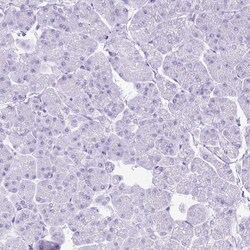

| Immunohistochemistry (Paraffin), Western Blot, Immunocytochemistry | |